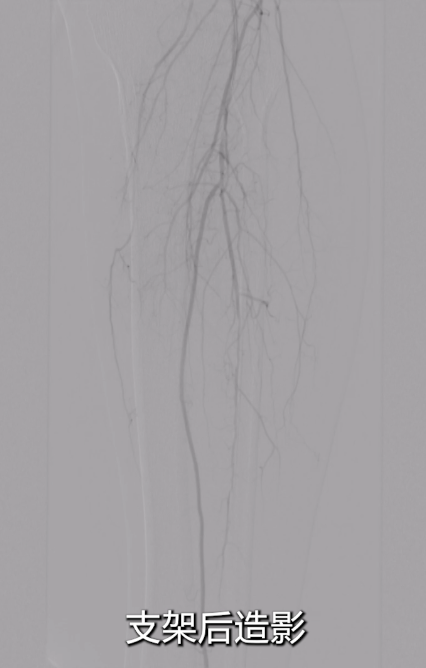

术后效果

即时造影:支架贴壁良好,病变段完全覆盖,膝下腓动脉及胫后动脉显影明显改善,胫后动脉血流可至足趾;

术后ABI:左侧ABI从术前0.32升至0.67,右侧1.09;患者症状改善,左足皮肤发紫发黑明显缓解,静息痛消失。

术后1月复查CTA,血管通畅性良好。给予双通道抗凝+抗血小板治疗,预防血栓再形成。